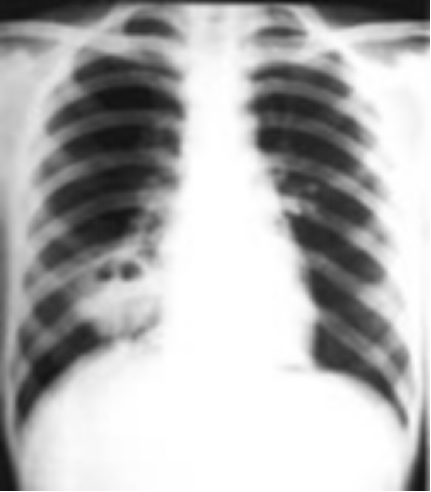

白色念珠菌肺炎

(candida pneumonia)

4 岁女孩患感染性肉芽肿,

合并肺炎。卧位胸部 X 线

检查见:

-双侧致密中等大小班片阴影

-右侧肺门大片致密阴影

-肺部透亮度增加,尤其是基底部

卡氏肺囊虫所致间质性肺炎

4 岁半女孩患卡氏肺囊

虫所致间质性肺炎(心脏

手术后)胸部 X 线检查:

典型均一性毛玻璃状浑

浊,下野特别明显